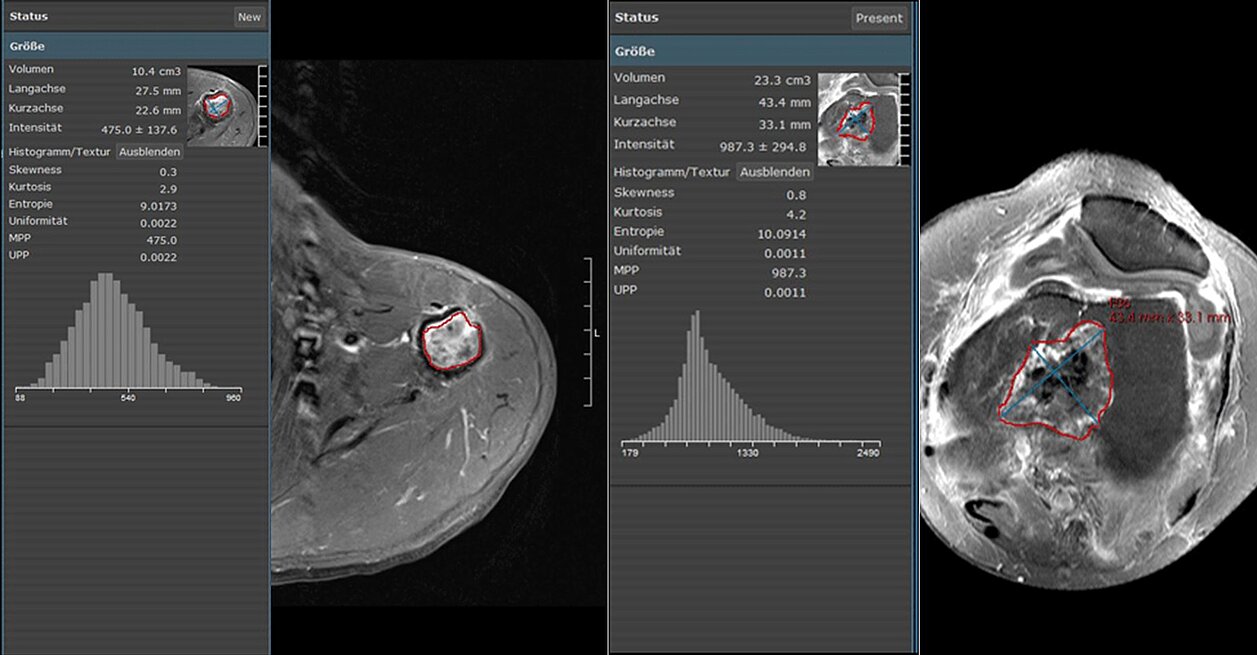

22 Patienten wurden nachträglich evaluiert: 11 Patienten mit einem Low-Grade-Chondrosarkom und 11 Patienten mit einem Enchondrom. Die Texturanalyse wurde auf vier MRT-Sequenzen in mint Lesion vorgenommen. Kurtosis, Entropie, Skewness, Mean of positive Pixels (MPP) und Uniformity of positive Pixel Distribution (UPP) wurden ermittelt und mit der Histopathologie in Korrelation gebracht.

Die Ergebnisse zeigen, dass deutliche Unterschiede bei vier von 20 Texturparametern in Bezug auf die verschiedenen MRT-Sequenzen gefunden wurden (p < 0,01). In den T1-gewichteten Serien mit Kontrastmittelgabe lagen die Werte für die Area under the curve (AUC) zur Unterscheidung von Chondrosarkom und Enchondrom bei 0,876 für Kurtosis und 0,826 für Skewness. In den T1-gewichteten Serien ohne Kontrastmittelgabe lagen die Werte bei 0,851 bei Entropie und 0,822 bei UPP. Die höchste Trennschärfe zeigte sich bei Kurtosis bei T1-gewichtet mit Kontrastmittel mit einer hohen Sensitivität (82%), Spezifizität (91%) und Genauigkeit (86%).